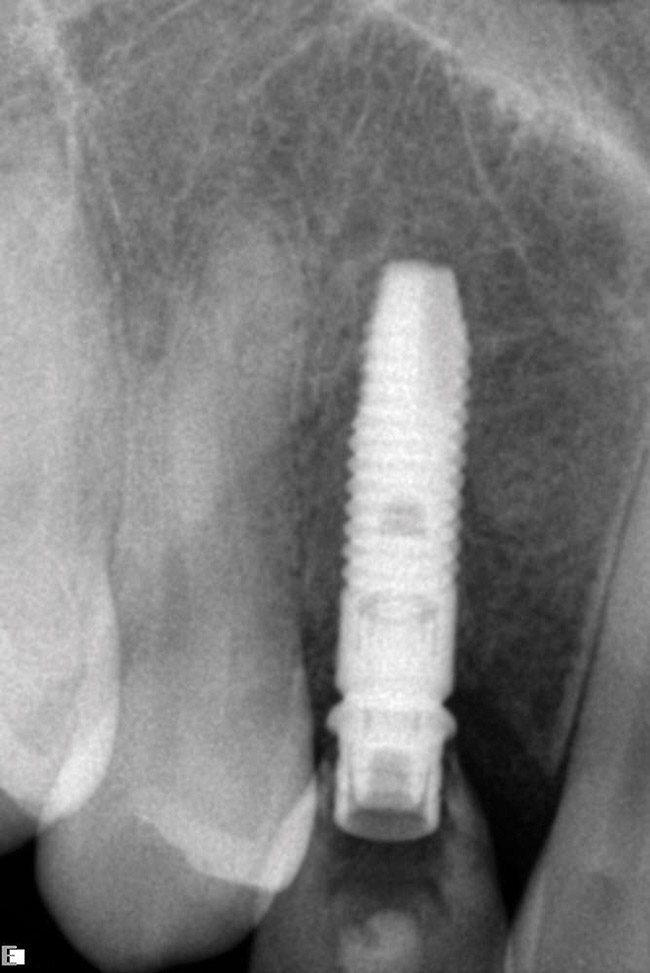

Figure 8  Primary stability of the implant achieved, facilitating a transmucosal healing approach.

Figure 8

Figure 9  Primary stability of the implant achieved, facilitating a transmucosal healing approach.

Figure 9

Approximately 4 months after grafting, the patient returned for clinical and 3-D radiographic evaluation. The thinnest area of ridge width preoperatively was remeasured in approximately the same location, demonstrating a gain of about 4 mm (Figure 7). The treatment plan was to place a 3.5-mm x 13-mm implant with a computer-generated guide (SiCat, Sirona Dental, www.sironausa.com), eliminating an additional open surgical procedure. Planning included initial osteotomy preparation with single-use drills combined with a localized ridge expansion using narrow, tapered osteotomes. This was performed approximately 5 months after the augmentation procedure, achieving primary stability of the implant, facilitating a transmucosal healing approach (Figure 8 and Figure 9). Following each step of osteotomy preparation, a probe was inserted along the walls of the site to confirm the integrity of the buccal and palatal walls prior to implant insertion.